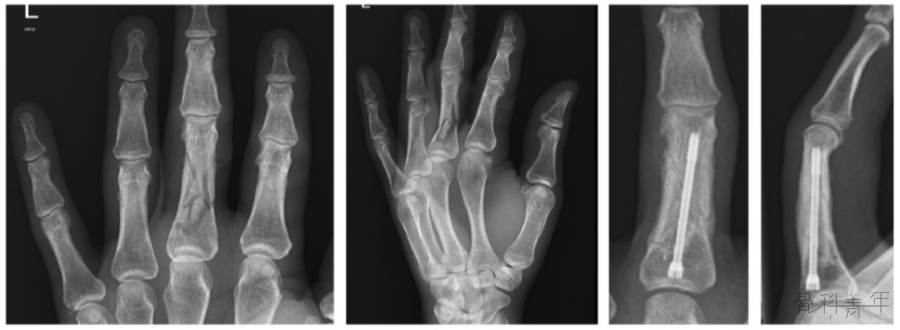

掌骨、指骨骨折的治疗方法众多,国外学者采用无头加压螺钉固定关节外不稳定的掌指骨骨折,取得了良好效果。该手术方案不影响关节活动,微创置入,利于早期功能锻炼,有效降低了并发症的发生。

掌骨、指骨骨折的治疗方法众多,包括经皮克氏针、钢板、拉力螺钉等,各种固定方式各有优劣,尚无金标准。上述各方案术后并发症如关节僵硬、屈曲挛缩和肌腱激惹等发生率仍较高,甚至需要二期手术治疗。

针对上述问题,国外学者采用无头加压螺钉固定关节外不稳定的掌指骨骨折,取得了良好效果。该手术方案不影响关节活动,微创置入,利于早期功能锻炼,有效降低了并发症的发生。

1.逆行髓内螺钉技术

该技术的指征为掌骨干的横向骨折,也适用于非粉碎的头下骨折和短斜形骨折。注意:在术前应测量好所用螺钉的长度和直径。手术方法:1.闭合复位。掌指关节 (MCP) 屈曲 90°,在 MCP 关节上作一长约 3.0 mm的纵向切口;2.在透视下沿掌骨轴线插入导丝。进导丝位置位于掌骨头背侧,以利于螺钉置入;3.置入无头空心加压螺钉,通常直径为3.0mm。有学者建议将螺钉置入达掌骨峡部以确保牢固固定。为了最大程度地减少软骨损伤,建议即使对于峡部可以用 5.0mm螺钉的第五掌骨,也使用 3.0 mm螺钉。在这种情况下,骨折保持相对稳定、可间接愈合。注意:螺纹应完全跨过骨折处(图1)

图1 髓内螺钉固定掌骨横行骨折。

2.“Y”型支撑技术横行骨折采用单枚螺钉可以取得良好效果,但对于粉碎性骨折,采用单枚加压螺钉可能会破坏结构的稳定性,因此有学者提出了“Y”型支撑(注:使用2颗螺钉(3.0 mm和 2.2 mm)构建三角形结构,以支撑骨骼并防止结构塌陷的技术方法(图2)。

图2 “Y” 型支撑技术治疗多节段、粉碎的掌骨骨折。02